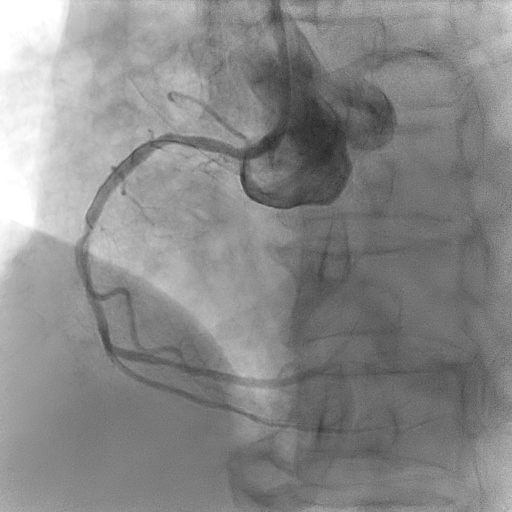

Relevant Catheterization Findings

Coronary angiogram showed two vessel disease with severe stenosis at the obtuse marginal (OM), distal left circumflex (LCx) artery and distal right coronary artery (RCA) with mild disease at the proximal left anterior descending artery (LAD).

Using guide EBU 3.0/6Fr, RTF crossed lesion OM and predilated with SC 2.0/12mm 8-12atm, then Scoreflex 2.5/15mm upto 20atm. DCB (distal LCx) with Agent 2.5/20mm at 8atm then DES (OM) with Synergy 2.5/24mm at 11atm followed by postdilatation using NC 2.75mm at12-20atm. Using guide JR 3.5/6F, coronary wire RTF to distal RCA, sequential predilatation with SC 2.0/12mm at 10-12atm then Wedge 2.5/15mm at 16-18atm. DCB with Pantera Lux 2.5/20mm at 8atm. Final angiogram showed TIMI III Flow, No dissection. Further evaluation with Cardiac MRI showed increased pericardial signal at the mid-apical lateral wall and part of the mid anterior wall on STIR-T2 study. In the late phase of gadolinium study, there is near transmural enhancement of the basal-apical lateral wall, partially extending into the inferior wall. The overall findings are in keeping with ischaemic cardiomyopathy, complicated with pericardial effusion and mild pericardial effusion and inflammation likely related to Dressler¡¯s Syndrome.